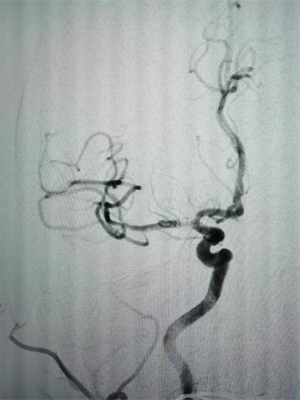

元宵节凌晨4点,60岁的胡先生因左侧肢体无力、言语不清,被紧急转送至我院。经检查,胡先生右侧脑梗死,且仍有大片缺血低灌注区域,右侧大脑中动脉完全闭塞,情况十分危急。神经内科介入团队迅速启动卒中绿色通道,立即为其行大脑中动脉急诊再通手术。术中,医生通过球囊扩张并置入血管支架,成功实现血管再通。当晚,胡先生左侧上下肢无力症状明显改善,肢体力量恢复,言语也变得清晰。

△图一:手术前右侧大脑中动脉闭塞